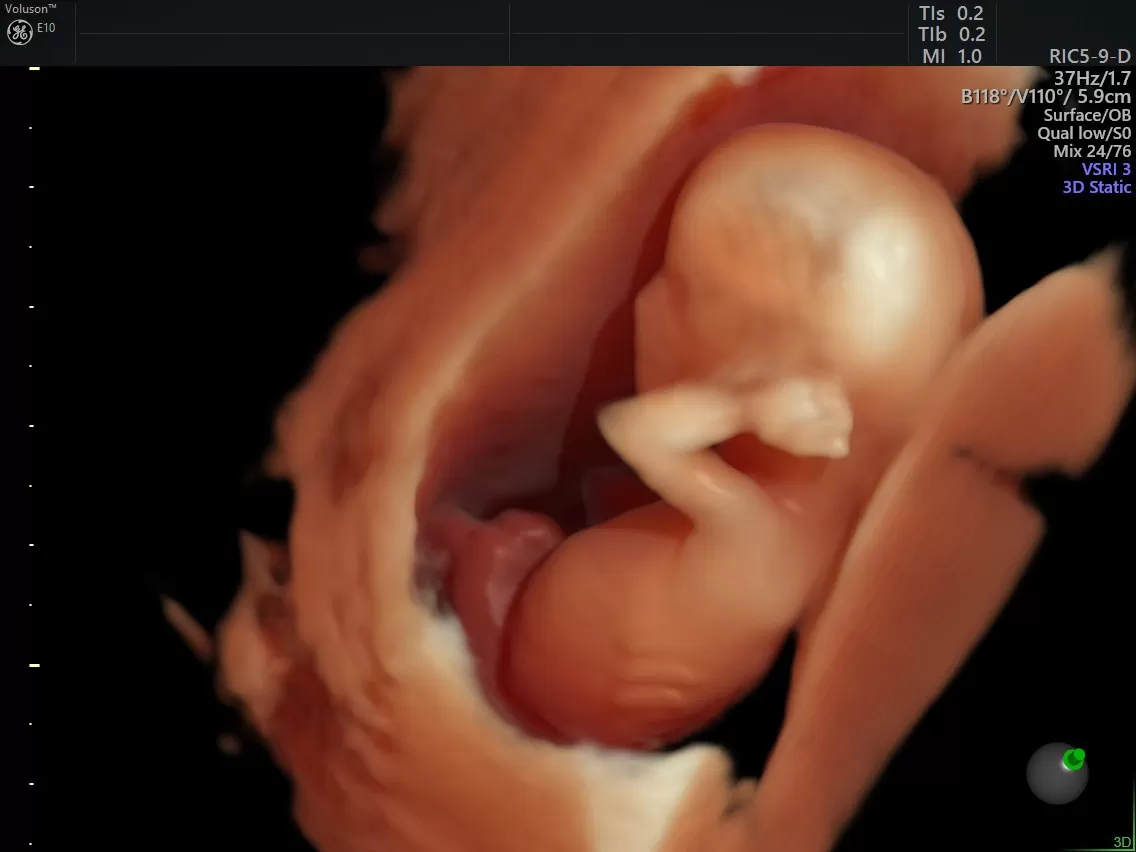

Сегодня медицина дает женщинам всё больше возможностей для реализации материнства, даже в возрасте, который еще недавно считался репродуктивно неблагоприятным. ЭКО после 50 лет — не редкость. Однако за этим стоит целый комплекс медицинских нюансов, о которых важно знать заранее.

Женщина может вступить в программу ЭКО и после 50 лет, особенно если менструальный цикл ещё сохраняется. Однако даже при этом шансы на успех с использованием собственных яйцеклеток равны нулю. В таких случаях единственным методом считается ЭКО с донорскими яйцеклетками. Это означает, что для зачатия используются клетки молодой здоровой женщины донора. Оплодотворение происходит методом ЭКО в лабораторных условиях, и далее эмбрион переносится в матку женщины-пациентки.

Существует два способа получить эмбрион – с использованием собственных половых клеток пары или донорских. Для беременности в старшем возрасте преимущество отдается методике ЭКО ИКСИ, когда сначала подбирают ооциты и сперматозоиды, а затем в лаборатории проводится их слияние под контролем специалистов. Такой подход дает возможность заранее отобрать здоровые клетки (без генетических отклонений) и оплодотворить яйцеклетку с помощью инъекции. Это позволяет достичь максимально положительных результатов и внушает надежду на материнство тем, кто еще думает, можно ли в 50 лет сделать ЭКО.